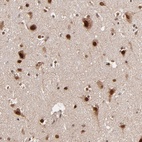

Immunohistochemical staining of human cerebral cortex shows strong nuclear and cytoplasmic positivity in neuronal cells.